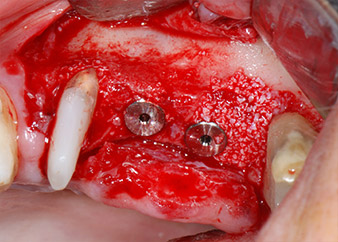

Im folgenden Schritt wurde das jeweilige Implantatbett an den Positionen 25 und 26 mit rotierenden Instrumenten in einem Winkelstück mit einem Übersetzungsverhältnis von 20:1 (WS-75 L G, W&H) und einem vor Kurzem aktualisierten leistungsstarken Implantatmotor präpariert (Implantmed, W&H) (Abb. 8 und 19).

Vor der Insertion der Implantate und nach Überprüfung der intakten Schneiderschen Membran (Abb.9) wurde der interne Sinusboden an beiden Implantatpositionen mittels eines xenogenen Knochenersatzmaterials (Abb. 10) augmentiert.

Dann wurden die Implantate (Restore, Keystone Dental) mit dem Implantatmotor eingesetzt (Abb. 11 und 12).

Insertion des Implantats an Position 26

Abb. 11: Insertion des Implantats an Position 26 bei geringer Geschwindigkeit und einer Drehmomentbegrenzung von 35 Ncm.

Eindrehen der Abdeckschrauben

Abb. 12: Beide Implantate sind in Position und bereit für das Eindrehen der Abdeckschrauben.

Knochendefizite an der mesialen Fläche des Zahns 27 und an der bukkalen Wurzel des Zahns 24 wurden mit xenogenem Knochenersatzmaterial aufgefüllt und mit einer resorbierbaren Kollagenmembran (Geistlich Bio-Gide) im Sinne einer GBR-Augmentation (Abb. 13 und 14) abgedeckt.